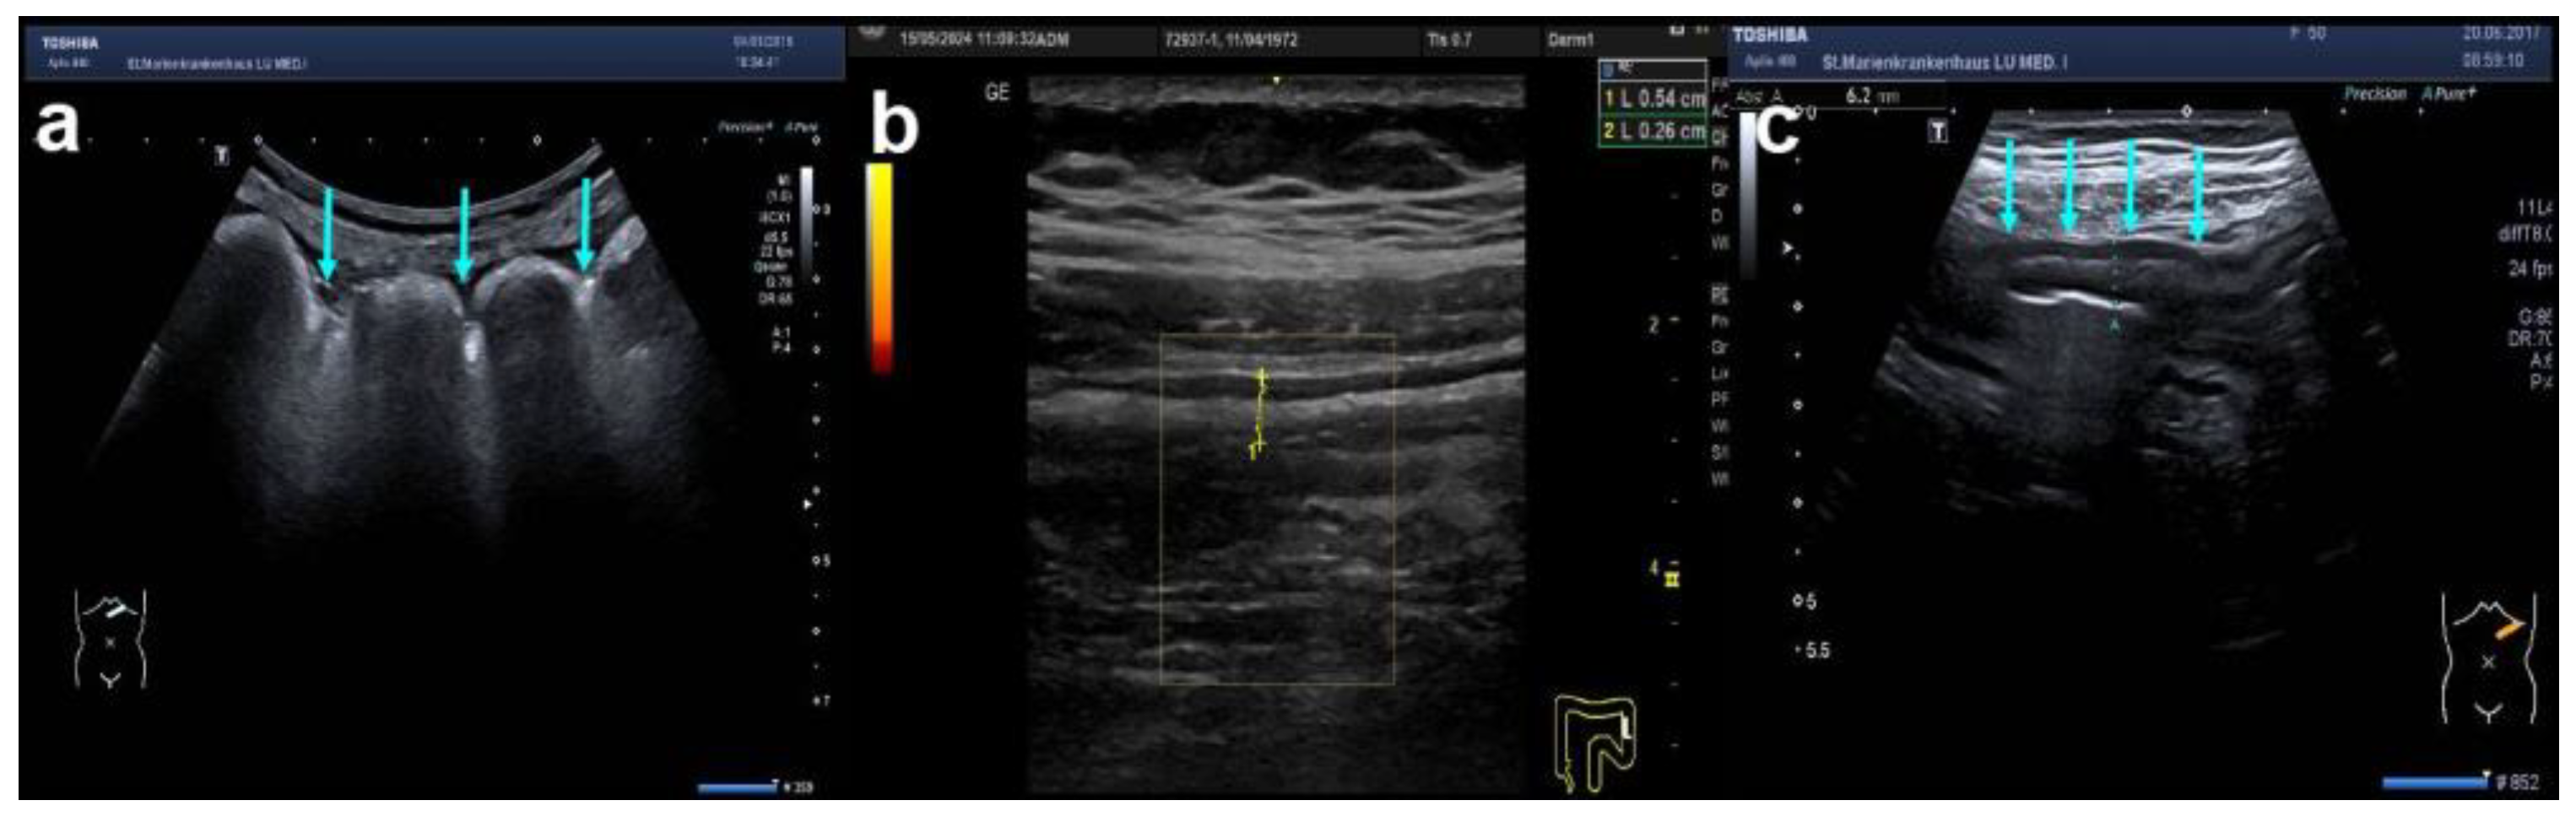

| Luminal changes | Small bowel dilatation | [present; absent (lumen diameter > 25 mm)] | |

| Luminal narrowing (small bowel) | [present; absent (lumen diameter < 10 mm)] | ||

| Stricture length | (small bowel luminal narrowing) | [present (in mm for luminal narrowing); absent] | |

| Surrounding | Peri-intestinal fat (creeping fat) | (inflammatory fat or iFAT) | [normal; slightly increased hyperechoic tissue; markedly increased hyperechoic tissue] |

| Fluid (hypoechoic or echofree) | [little interenteric (<20 mm); large, localised (>2 cm); free ascites] | ||

| abscess (hypoechoic area, no CDS) | [present; absent] | ||

| fistula (hypoechoic tract) | [present; absent] | ||